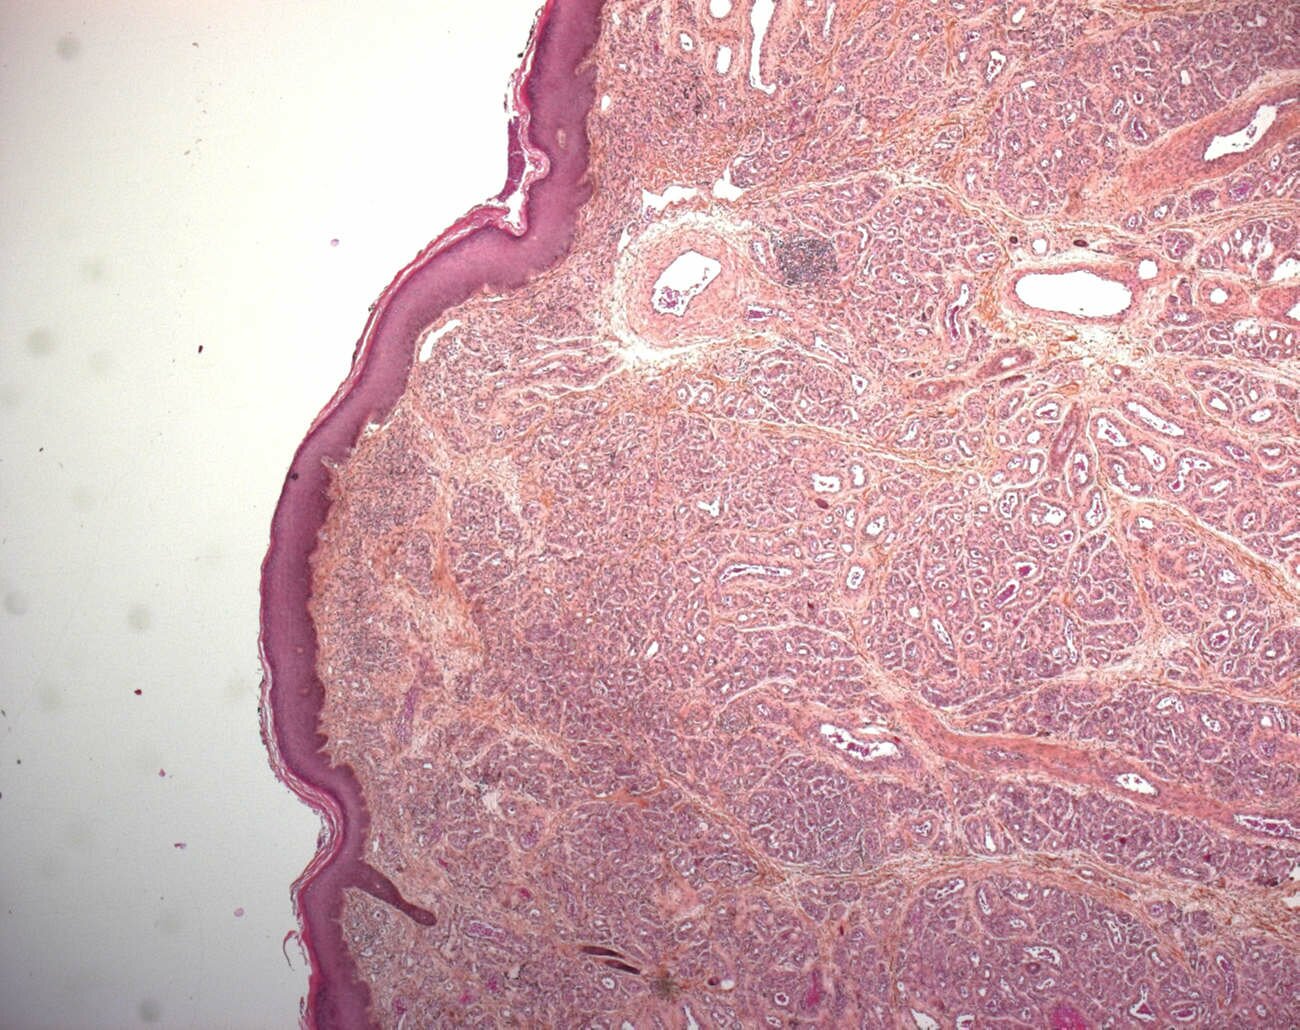

These tumors are highly cellular, involving the dermis, often with extension into the subcutis. The tumor has a lobular architecture and plump endothelial cells. The latter cells express glut-1 antigens throughout the life of this tumor.

lobular architecture